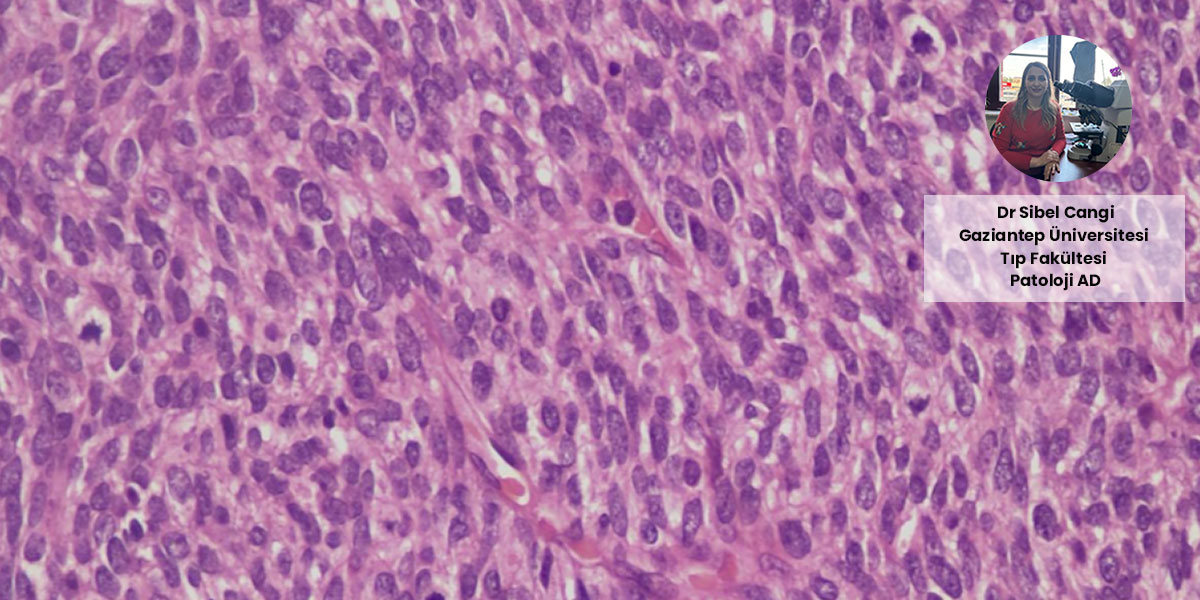

Dr. Sibel Cangi